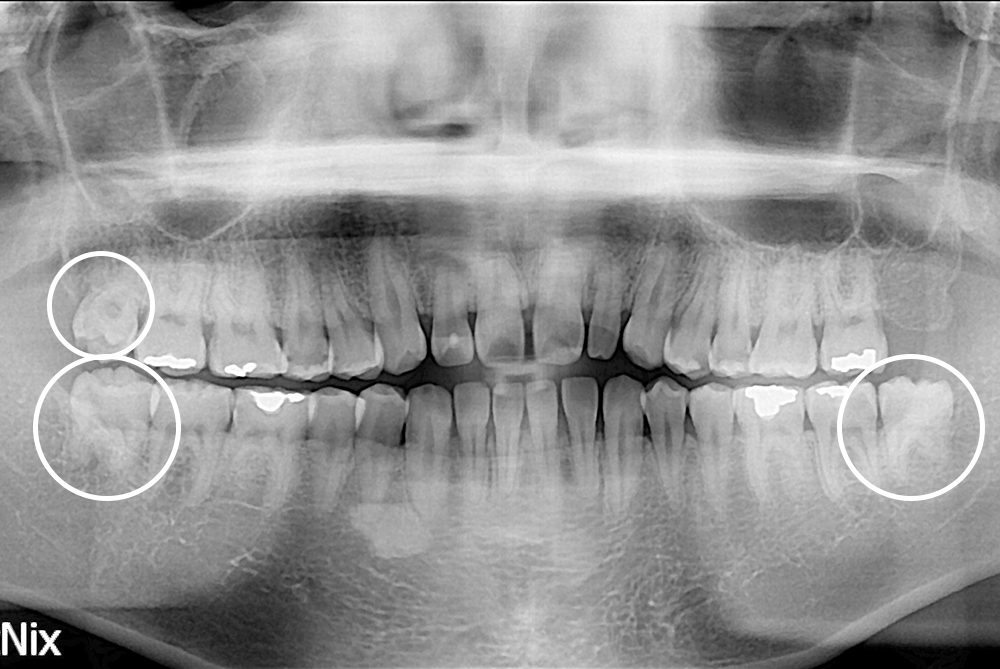

[사랑니] 매복 사랑니 발치

치료전 : 2019-07-16